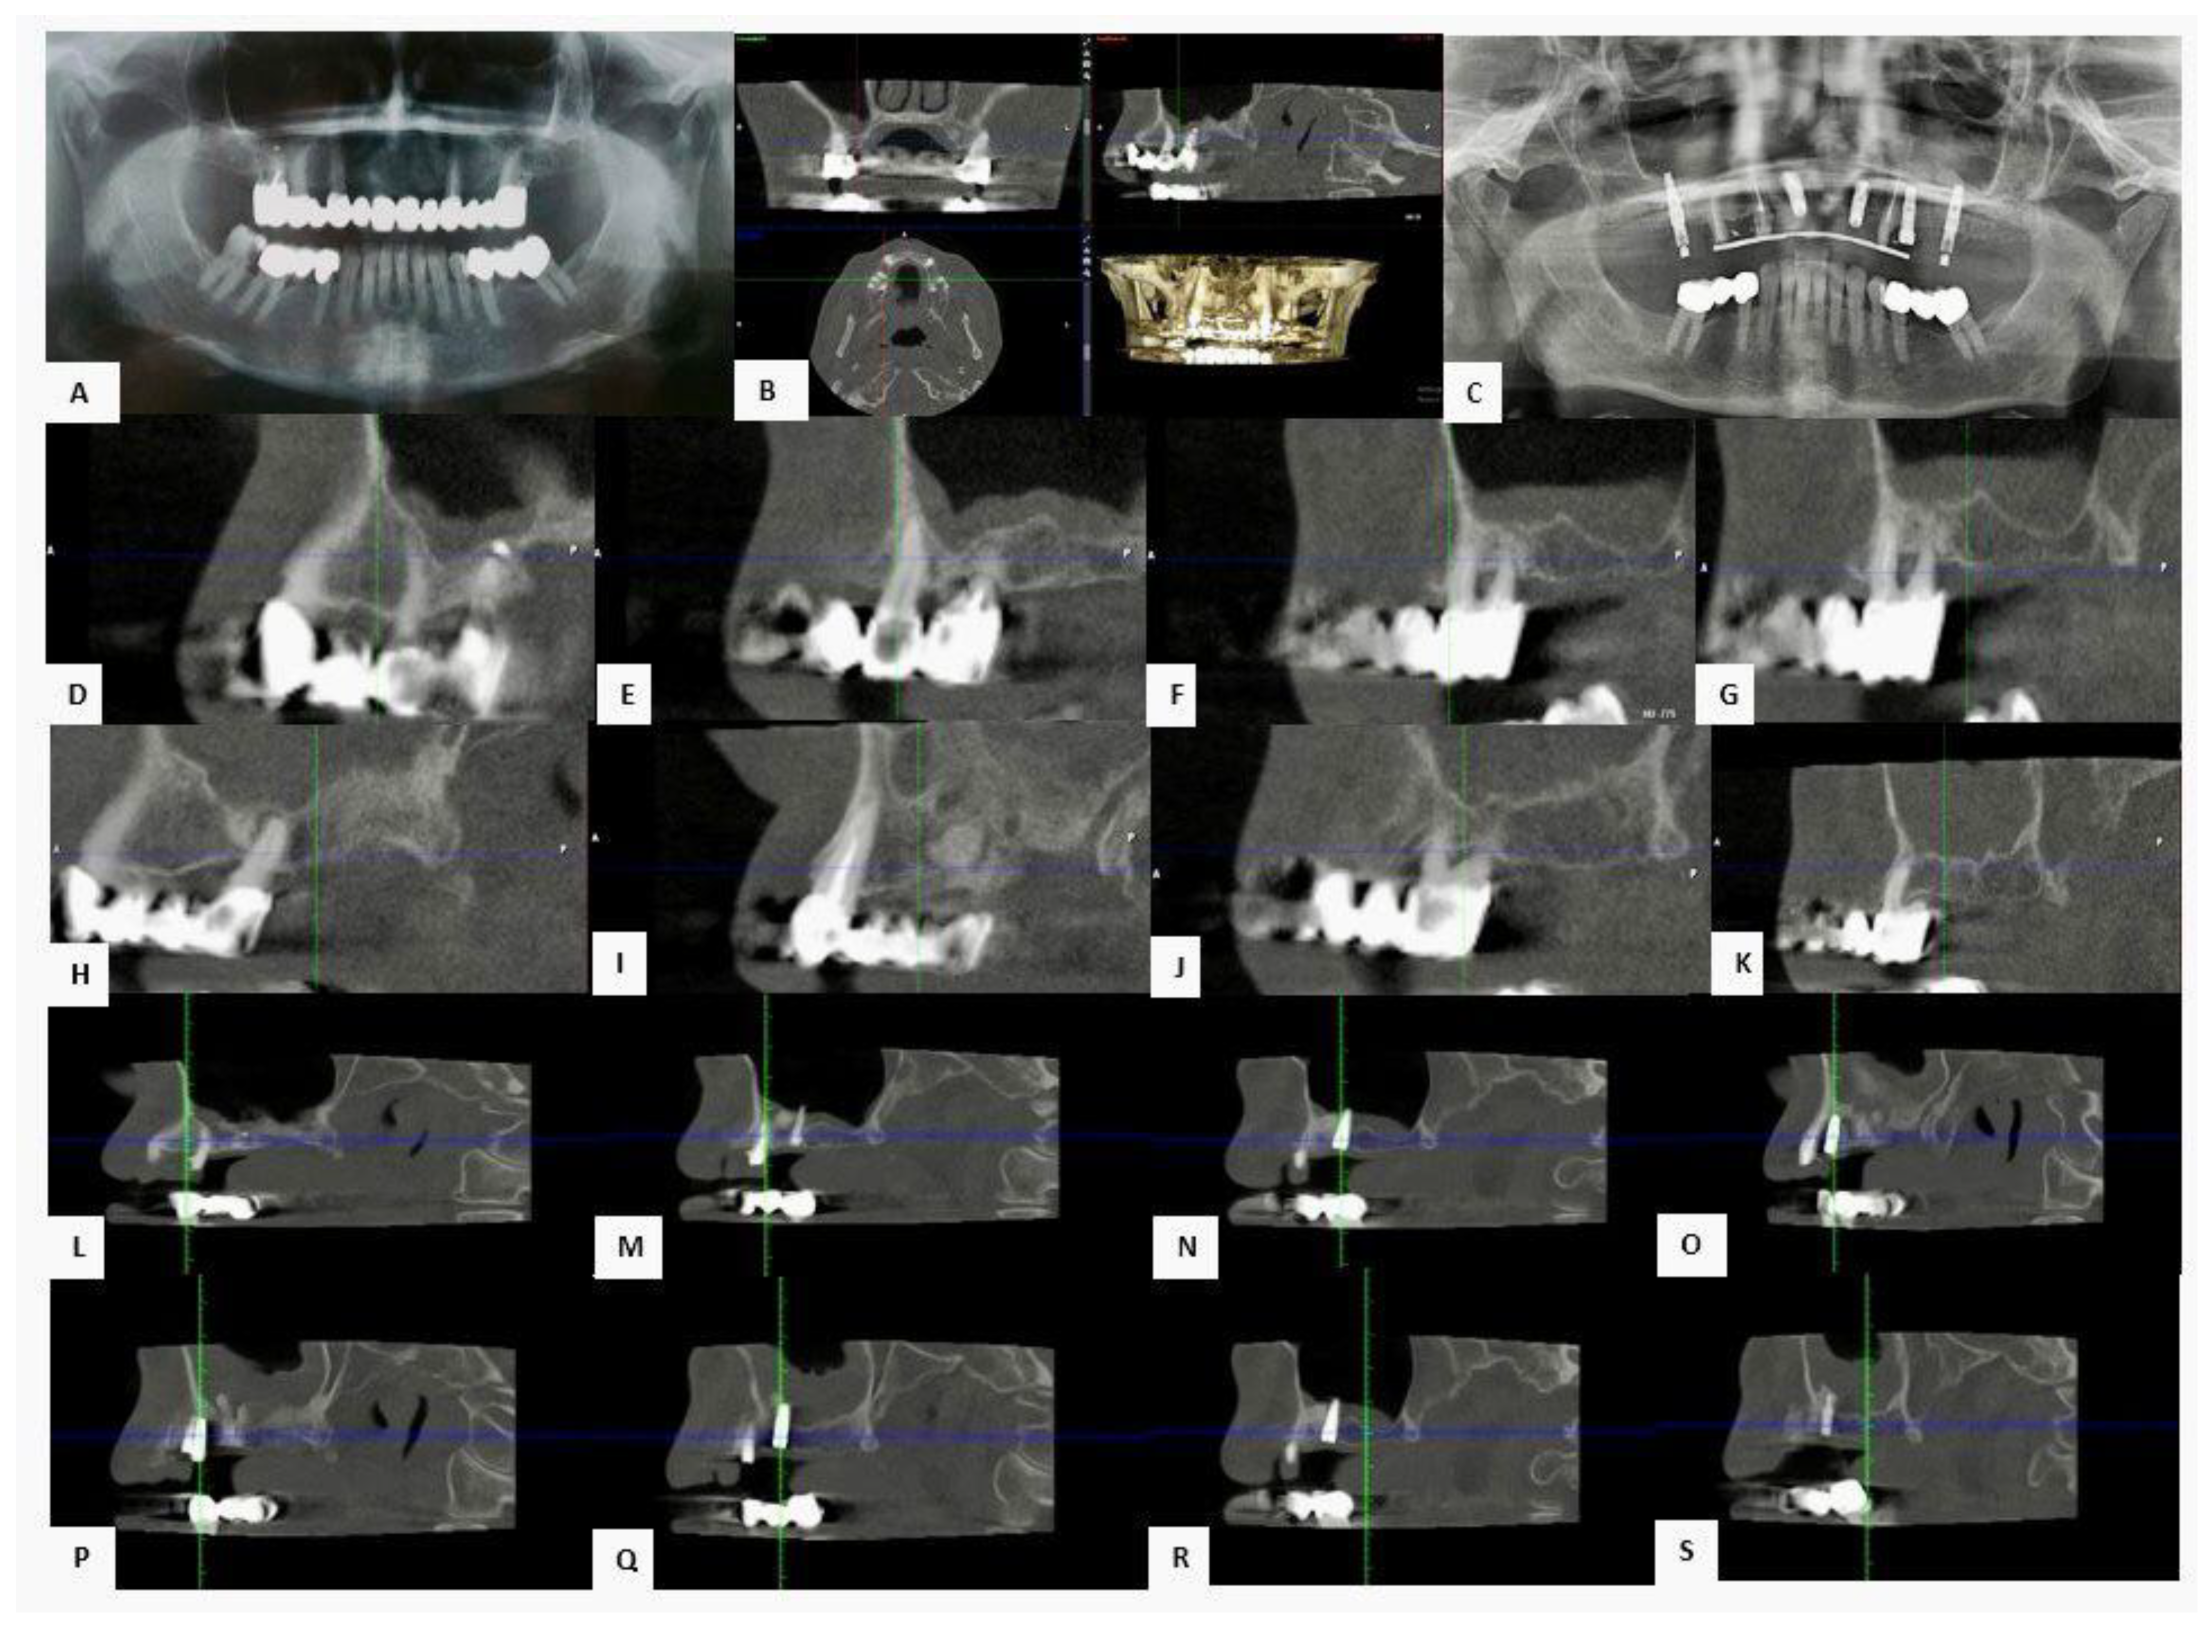

3.3.1. Case 1—Female Patient, 52 Years Old

3.3.2. Case 2—Female Patient, 60 Years Old

3.3.3. Case 3—Male Patient, 58 Years Old

4.2. Considerations on Representative Clinical Cases